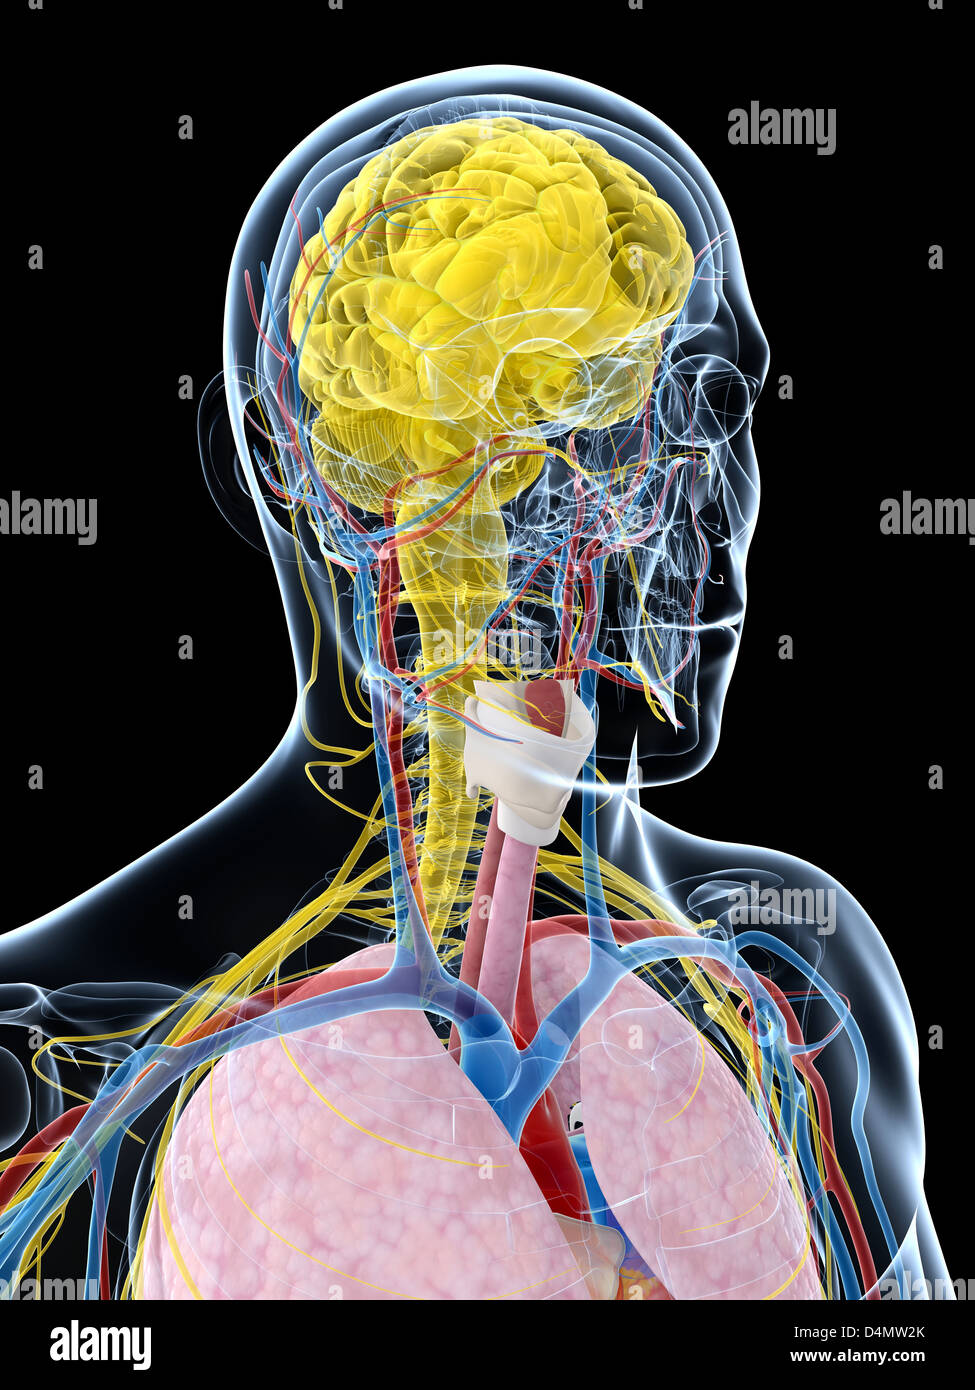

RF2N9P3NT–Röntgen des Schilddrüsenknorpels 3D-Darstellung mit männlichen Körperkonturen. Menschliche Anatomie, Medizin, Biologie, Wissenschaft, Gesundheitskonzepte.